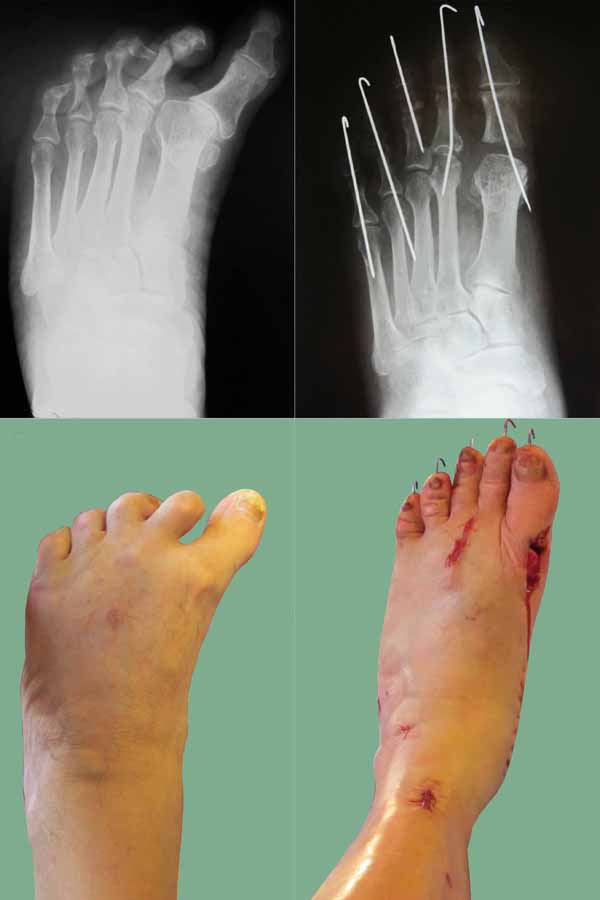

Могу сообщить из личного опыта. Больной 65 лет, страдает артрогрипозом. Стопы не оперированы. Рентген аналогичный. Деформация стопы многокомпонентная многоплоскостная: эквино-поло-варусная, приведение переднего отдела, варусная когтеобразная деформация 1 - 5 пальцев.

Выполнено:

1) удлинение ахиллова сухожилия по Байеру;

2) Z-обр. удлинение сухожилия задней большеберцовой мышцы, транспозиция сухожилия передней большеберцовой мышцы на наружный край стопы;

3) пересечён подошвенный апоневроз;

4)Z-обр. удлинено сухожилие длинного сгибателя 1 пальца, тенотомия сухожилия сгибателей 2 - 5 пальцев;

5)транспозиция сухожилия длинного разгибателя 3 п. на длинный разгибатель 2 п. с удлинением, транспозиция короткого разгибателя на длинный 3 п. с удлинением;

6) капсулотомия 2 - 3 ПФС, круговой релиз 1 ПФС;

резекция основания проксимальной фаланги 1 п.

Фиксация 1 - 5 пальцев осевыми спицами. Лонгета. Ближайший результат на фото (операция 8 дней назад).